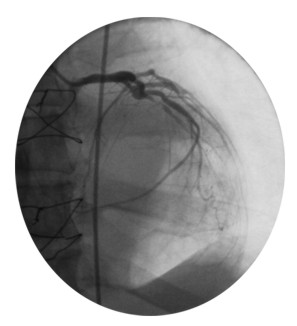

catéter se puede hacer avanzar hacia las arterias coronarias e

inyectar un colorante en las mismas (Angiografía o

Arteriografía Coronaria). Mediante el uso de un fluoroscopio (un

tipo especial de rayos X), el médico puede ver dónde

están obstruidas las arterias coronarias, observando el

segundos. El catéter se podría hacer llegar a las

arterias coronarias, donde se inyecta un colorante para determinar

si

existen obstrucciones y, si es que existen, dónde están

localizadas.